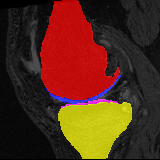

Knee MRI experiment: We test our method on 3D knee MRIs from the Osteoarthritis Initiative (OAI) 111https://nda.nih.gov/oai/ and corresponding segmentations of femur and tibia as well as femoral and tibial cartilage [1]. From a total of 507 labeled images, we use 200 for training, 53 for validation, and 254 for testing. To test registration performance we use 10,000 random image pairs from the test set. All images are affinely registered to an atlas built from the training images, resampled to isotropic spacing of 1mm, cropped to and intensity normalized to [0,1]. In addition, right knee images are flipped to be consistent with left knees. For training, the loss weights are , , and based on approximate hyper-parameter tuning. Note that when computing from the displacements, the image coordinates are scaled to [-1, 1] for each dimension following the convention in the interpolation function of PyTorch.

Results: All trained networks are evaluated using Dice overlap scores between predictions and the manual segmentations for the segmentation network, or between the warped moving segmentations and the target segmentations for the registration network. Tabs. 1 and 2 show results for the knee and brain MRI experiments respectively in Dice scores (%). Fig. 2 shows examples of knee MRI registrations and brain MRI segmentations.

Knee results: On knee MRIs, our method improves segmentation scores over separately learned networks by about 1.2 and 0.5, and registration scores increase by about 3.1 and 3.0, when training with 5 and 10 manual segmentation respectively. Especially for the challenging cartilage structures, our joint learning boosts segmentation by 1.4 and 0.7, and registration by 5.5 and 5.2 for N=5 and N=10 respectively.

Qualitative results: DA achieves more anatomically consistent registrations than the mono-networks on the knee (Fig. 2) and Brain MRI samples (see supplementary material).